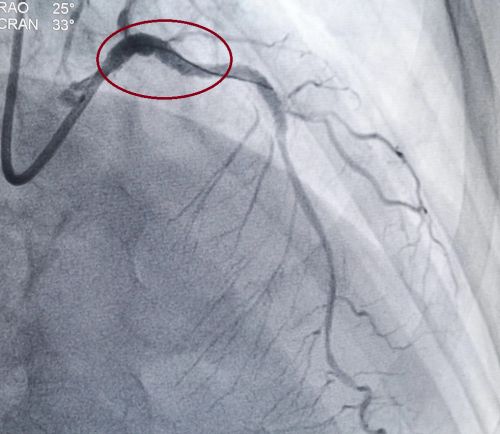

经过反复球囊扩张及药物支架置入后,左主干无狭窄。